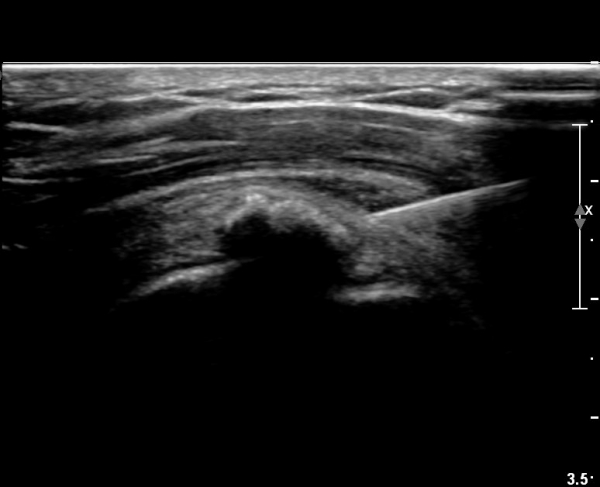

ÃÊÀ½ÆÄ ¼Ò°ß :  ±Ø»ó°Ç Á¾´Ü¸é°Ë»ç¿¡¼­ ÈĹæÀ½¿µÀ» º¸ÀÌ´Â °í¿¡ÄÚ ¼®È¸È­ µ¢¾î¸®°¡ °üÂûµÈ´Ù(»çÁø 1).

±Ø»ó°Ç Ⱦ´Ü¸é°Ë»ç¿¡¼­µµ ±Ø»ê°Ç³» ¼®È¸È­ µ¢¾î¸®°¡ °üÂûµÈ´Ù(»çÁø 2).

±Ø»ó°Ç Á¾´Ü¸é °Ë»ç»ó¿¡¼­ Á¡¾×³¶³»¿¡ ÁÖ»ç¹Ù´ÃÀÌ À§Ä¡ÇÑ °ÍÀÌ º¸ÀδÙ(»çÁø 3).

Á¡¾×³¶³» ÁÖ»ç ÈÄ ÁÖ»ç¹Ù´ÃÀ» ¹Ýº¹ÀûÀ¸·Î ´õ ÁøÀÔ½ÃÄÑ ¼®È¸¸¦ ºÐ¼âÇÑ´Ù(»çÁø 4).